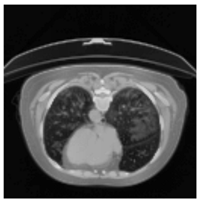

In Table 6, a comparison of the ground truth and prediction results of each model is presented in 2D, along with the 3D projection of each model. The visual analysis of the predictions provides additional insights into the performance of each model. The visualizations demonstrate that Attention UNet captures the intricate details of the lung construction more accurately, resulting in more precise segmentation of the infected areas compared to other models.

Table 6.

Comparison of ground truth and model prediction results using UNet, LinkNet, Attention UNet, UNet 3+, and TransUNet.